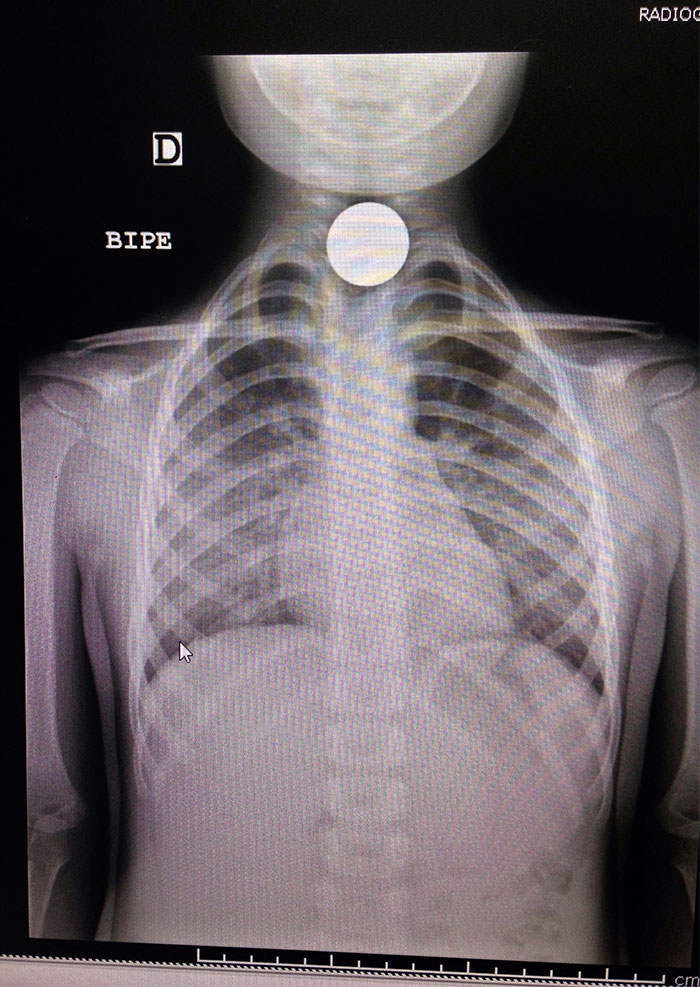

The Little Girl Swallowed A Coin

I had to go to the emergency room one time, the kid in the room next to us had a coin being removed out of her throat. the screams were terrifying even a room over.